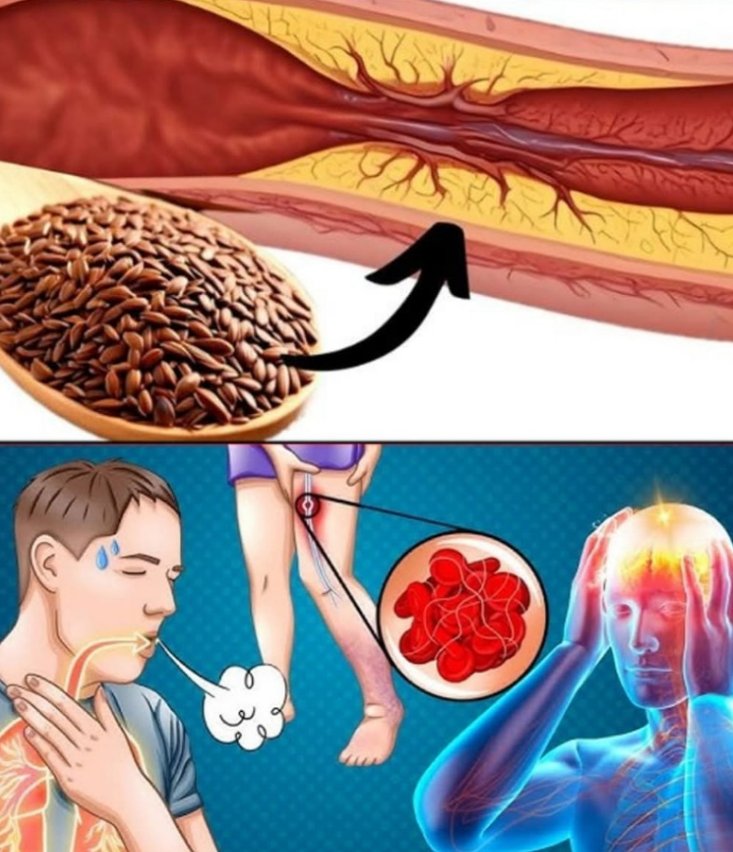

Wprowadzenie W świecie pełnym przetworzonych produktów i stresu, układ krążenia często jako pierwszy ponosi konsekwencje naszych codziennych nawyków. Dobra wiadomość? Istnieją naturalne składniki, które…